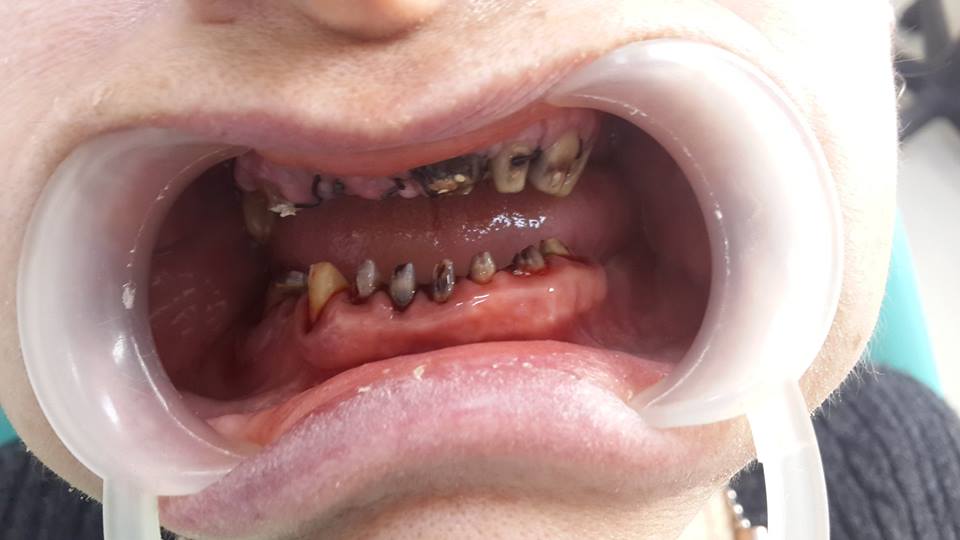

An example of complete rehabilitation of the oral cavity. Treatment included the removal of the old prosthesis, treatment of paradontitis, removal of a large cyst, implantation, clasp prosthesis.